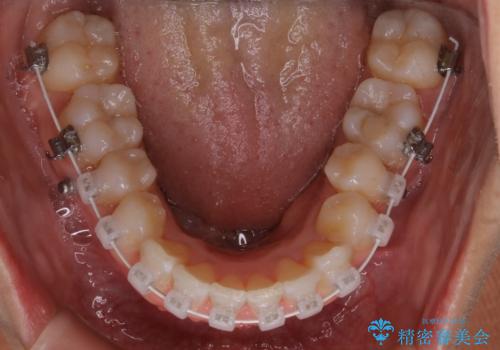

- ワイヤー矯正

左側のかみ合わせは、歯1本分かみ合わせが前にずれていました。上顎左右の奥歯を2本抜歯しています。

下顎は、歯の側面を少し削ることで歯並びを整えました。

上顎と下顎の奥歯の抜歯(計4本)を行う治療方法もありますが、口元のバランスのことも考え、上顎の抜歯のみで、治療を行いました。